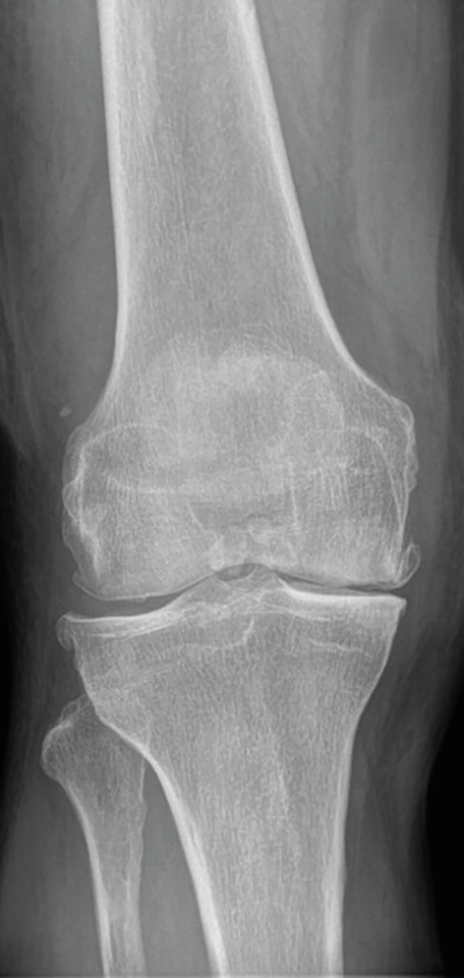

Obr. 2 Rentgenový obraz pokročilé gonoartrózyPro základní zobrazení a posouzení progrese poskytuje rentgenové vyšetření dostatečné informace o šířce kloubní štěrbiny, postavení artikulačních ploch, kvalitě subchondrální kosti a případných cystách či okrajových osteofytech. Je také pilířem radiologické diagnostické klasifikace stupně OA dle Kellgrena a Lawrence z roku 1957 – celkem pět stupňů, grade 0–IV, přičemž za přítomnou je považována OA grade II = s jistou přítomností osteofytů a možným zúžením kloubní štěrbiny.5 Příklad pokročilé gonartrózy ukazují obrázky 2 a 3.